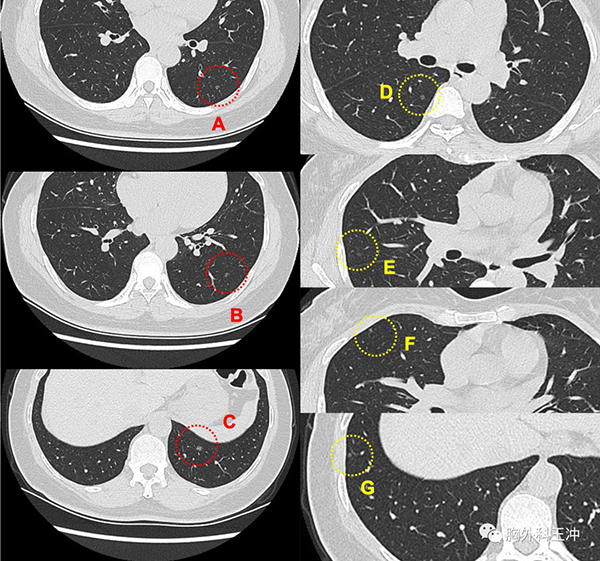

基本情况 女性,47岁,体检发现双肺多发磨玻璃结节1年,较大者位于左肺下叶。

手术方式 VATS左肺下叶切除、淋巴结清扫术

病理结果 病灶A:浸润性腺癌,0.5cm,腺泡型90%、贴壁型10%

病灶B:浸润性腺癌,0.6cm,腺泡型80%、贴壁型20%

病灶C:浸润性腺癌,0.8cm,乳头型60%、贴壁型40%

基因检测 exon2 KRAS

手术理由 1、形态典型,早期肺癌可能大;

2、较大者位于左肺侧, 左侧三处结节均在左下叶,故优先处理

3、右肺结节较小,可先观察

4、患者有手术意愿,希望明确诊断;

故进行左肺下叶切除。

下一步治疗 有基因突变但无对应药物,术后定期复查